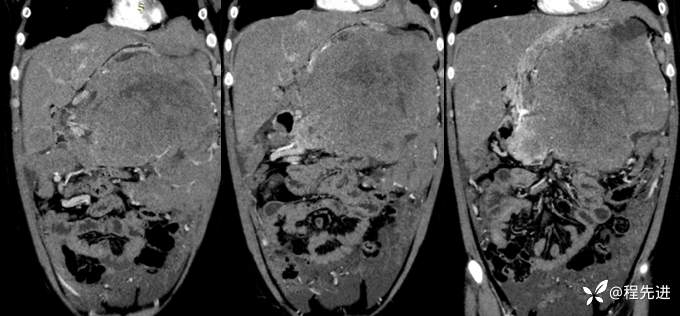

冠状位: